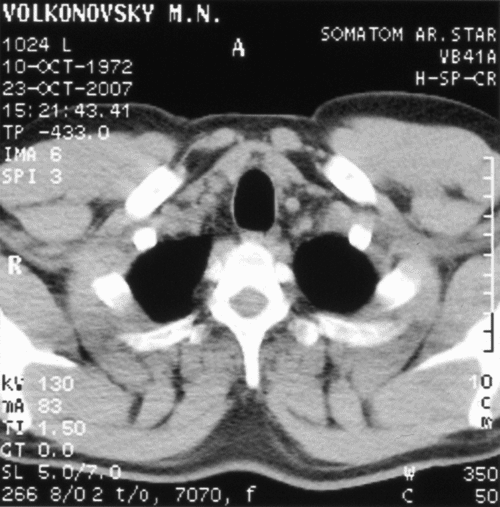

ЭКТ органов грудной клетки

Электронная компьютерная томография меня